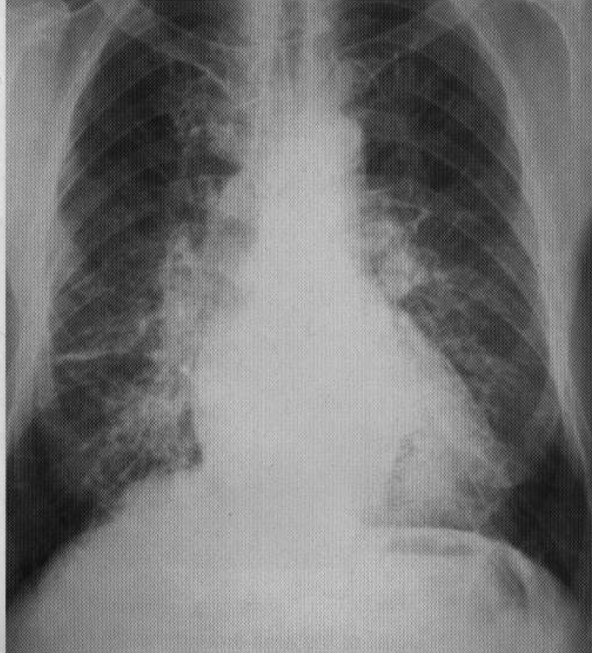

63 yo male smoker with history of dyslipidemia, HTN and myocardial infarction presents with increasing SOB of 1 week duration

View

DX

View: PA

DX: CHF, diffuse pneumonia, pulmonary edema